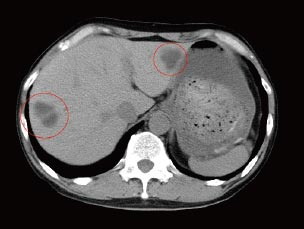

免疫治療前のCT検査

治療前CT(下の画像)では肝臓の右葉・左葉に存在する肝転移病巣が認められます。